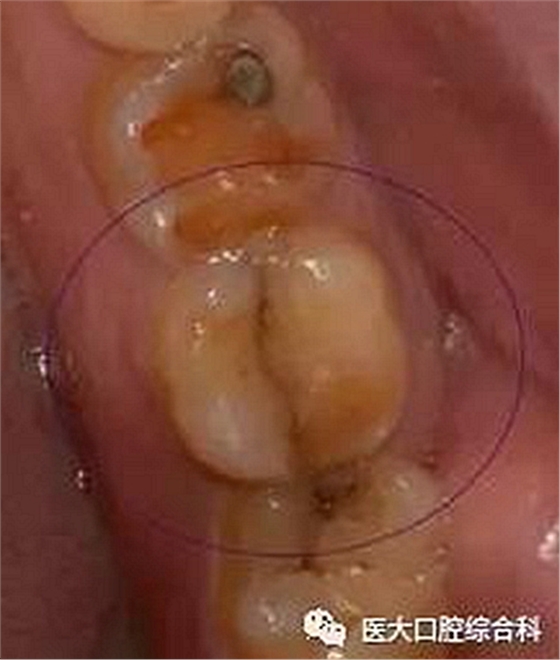

隱裂的位置多比較隱匿,常與天然窩溝的位置重疊,并向一側(cè)或兩側(cè)邊緣嵴延伸。